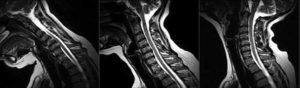

Die bekanntesten Untersuchungen sind die Kernspin- bzw. die Magnetresonanztomographie (MRT) und Gehörtests. Kernspintomogramme dienen dazu, die vorliegenden Tumoren darzustellen. Am häufigsten werden sie zur Untersuchung des Gehirns, der Wirbelsäule oder der Nerven der Arme und Beine angewandt.

Durch regelmäßig wiederholte MRT-Untersuchungen wird das Wachstum von Tumoren beobachtet. Kernspintomographische Untersuchungen führen nicht zu einer Belastung des Körpers mit Röntgenstrahlung.

Die Kernspintomografie stellt also das bildgebende Verfahren mit der derzeit höchsten Weichteilauflösung dar, so dass sie sich zur Darstellung von Gehirn, Rückenmark oder Muskulatur gleichermaßen gut eignet. Mit Hilfe eines Kontrastmittels kann außerdem Tumor- oder Narbengewebe, das sich z.B. nach einer Operation gebildet hat, hervorgehoben werden.

Mit offenen Systemen kann die Kernspintomografie auch während einer Operation eingesetzt werden. Selbst für erfahrene Neurochirurgen ist es oft außerordentlich schwierig bis unmöglich, intraoperativ die Grenze eines Tumors zu erkennen und entsprechend dieser Grenze eine „Totalentfernung“ des Tumors durchzuführen.

Eine Untersuchung mittels Kernspintomographie während der Operation trägt so unter Umständen dazu bei, dass der Tumor radikal, aber gleichzeitig schonend entfernt werden kann. Außerdem können Grenzen von Bahnsystemen und funktionelle Regionen im Gehirn dargestellt werden, die mit bloßem Auge unter dem Mikroskop nicht sichtbar sind.

Die Kernspintomografie bietet auch eine gute Möglichkeit, anhand der gewonnenen Informationen über Lokalisation und Ausdehnung des Tumors weitere Schritte in der Behandlung zu planen - zum Beispiel die Erstellung eines Bestrahlungsplans.